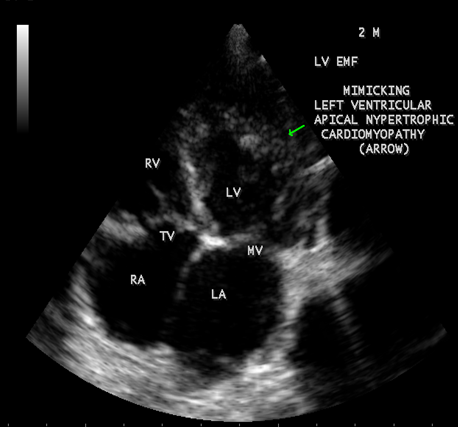

Case 6. Left ventricular endomyocardial fibrosis mimicking as Apical left ventricular hypertrophic cardiomyopathy in a 2- year old male child as shown in Figures 23 , 24 and 25.

Figure 23: (Left ventricular endomyocardial fibrosis mimicking as apical left ventricular hypertrophic cardiomyopathy in a 2- year old male child}

Figure 24: Apical four chamber view showing the endocardial fibrosis of the left ventricle in a 2-year old male child

Figure 25 Apical four chamber view showing diffuse endocardial fibrosis of left ventricle in 2-year old male child.

A left ventricular EMF mimicking apical left ventricular hypertrophic cardiomyopathy in a year-old boy as shown in Figures 23, 24 and 25 in a 2-year old male child and an apical right ventricular cardiomyopathy in a year-old female as shown in Figure 26 mimicking as right ventricular EMF have been found by Transthoracic echocardiographic screening. A right ventricular EMF associated with Psoriasis as shown in Figure 3 to7 in a 52- year old male and a left ventricular EMF associated with pemphigus in a 63- year old male as in Figure 39 were detected in this region of Thoothukudi.